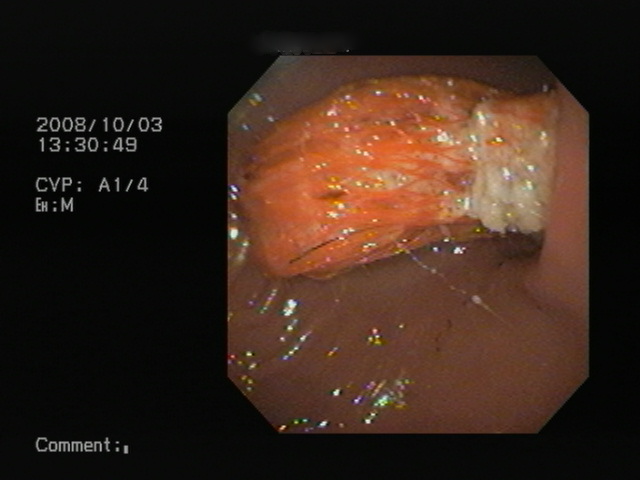

食道の心基部の写真です。黄色い物体が引っかかっている異物です。

これを異物除去鉗子で、除去を試みました。